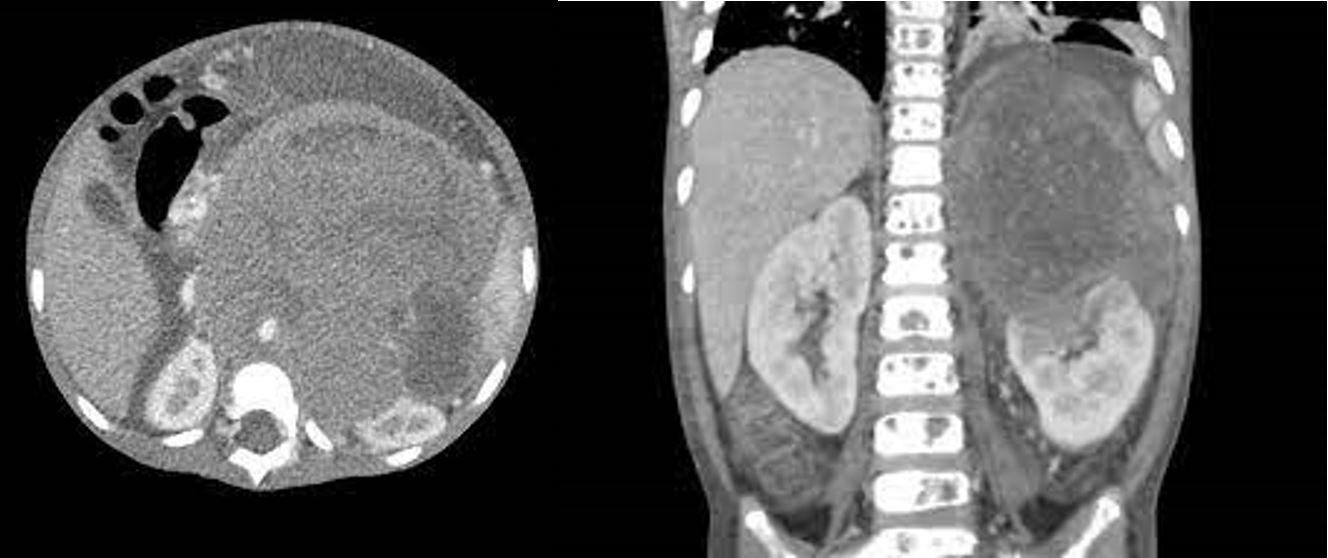

- Giai đoạn 4: U nguyên bào thần kinh ở giai đoạn này đã lan rộng đến các cơ quan quan trọng như não, gan, phổi và tim, gây ra các triệu chứng nghiêm trọng và có thể gây tử vong.

Chẩn đoán u nguyên bào thần kinh đệm được xác định bằng cách sử dụng các phương pháp chẩn đoán hình ảnh như MRI, CT scan và xét nghiệm tế bào u. MRI là phương pháp chẩn đoán tốt nhất để xác định u nguyên bào thần kinh đệm.